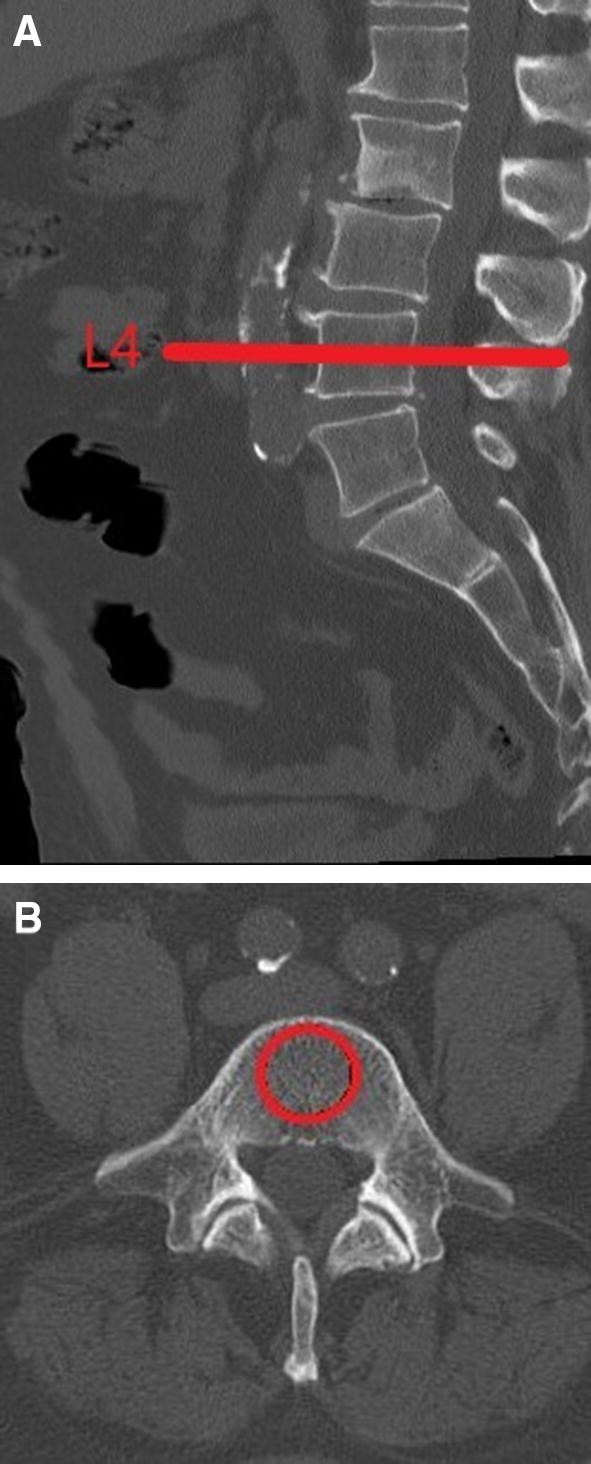

For each patient, CT vertebral body attenuation in a pre-defined region of interest (ROI) was recorded through trabecular bone in the L4, L5 and S1 vertebral bodies in Hounsfield units (HU). There was no initial step of plane angulation. The assessment was performed by placing a single oval over the trabecular bone in the axial view. The correct position in the middle of the vertebral body was double checked in the sagittal plane (see Fig. 1). The measurements were taken by a single rater on a standard PACS work station. The rater was blinded to the DXA results.

Fig. 1

figure 1

CT scan of the lumbar spine. Demonstration of HU measurement in the sagittal (a) and axial planes (b)